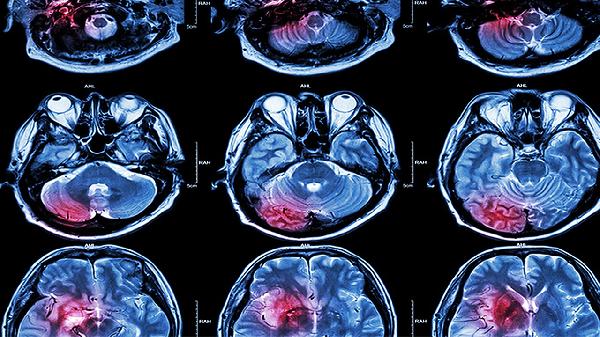

脑外伤注意事项有哪些 剖析脑外伤的五个注意事项

脑外伤的注意事项主要包括保持呼吸道通畅、监测意识状态、控制颅内压、预防感染和康复训练五个方面。